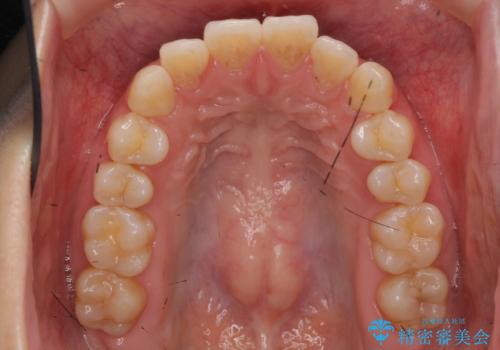

- 前歯のがたつきをきにされていました。

上下の前歯をやすりがけする処置(IPR)を行い、前歯の並びを出っ歯にしないようにしながら整えました。